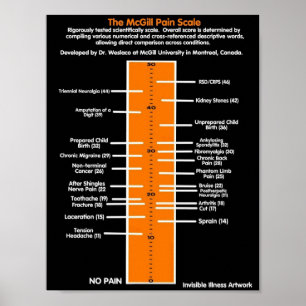

Poster Escala de dor de McGill dos POSTERS…

PreçoR$ 109,00